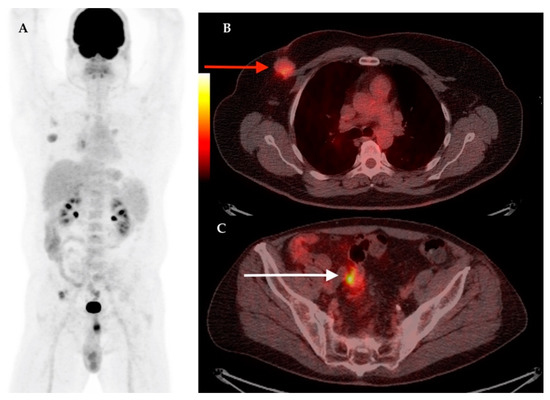

| 14 | 68 | IDC | RM + ALND | Yes | Yes | IIIB | LN | LN, Bn | 7.04 | Prostate cancer | 5.01– |

| 20 | 59 | IDC | RM + ALND | Yes | Yes | IIIB | – | LN, Sk | 8.6 | – | – |